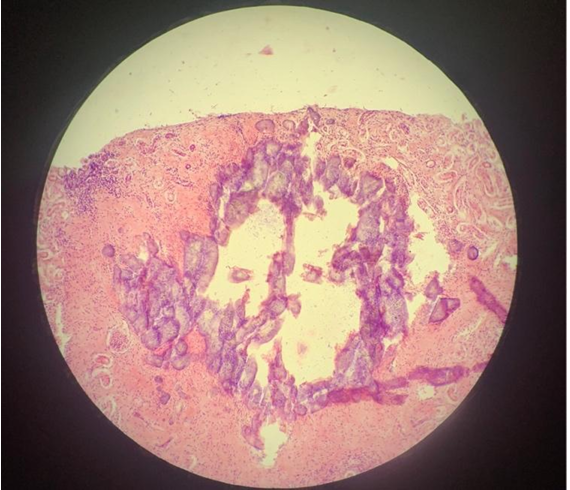

cholangitis et pericholangitis chronica hyperplastica (coccidiosis hepatis cuniculorum)

bile duct wall

papillary folds

coccidia

epithelial cells